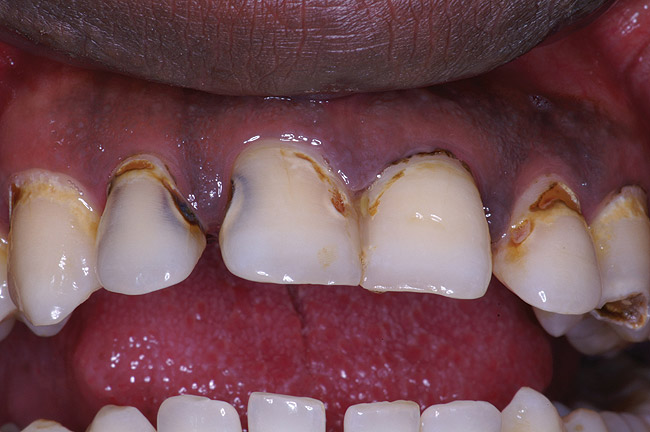

If a patient has risk factors that can contribute to dental erosion, an examination will reveal clinical signs and symptoms of dental erosion. It is unlikely that dental erosion will be seen without other contributing factors. Tooth wear and abrasion typically occur in combination with dental erosion. In the clinical evaluation of tooth surfaces for the diagnosis of erosion, what is typically seen are smooth, shiny surfaces of the teeth where the usual anatomic form of the tooth should be. In patients ingesting very acidic diets, the facial surfaces of anterior teeth are very smooth, and if the beverages being ingested have high sugar content, these teeth may have caries at their facial gingival margins (Figure 1). The occlusal surfaces of posterior teeth in the more advanced stages of erosion due to regurgitation may have extensive exposed dentinal areas with loss of anatomic form (Figure 2). In some cases, the chemical erosion combined with toothbrush–toothpaste abrasion can remove all the enamel, leaving only the dentin exposed (Figure 3). These teeth may exhibit sensitivity. Posterior teeth with restorations may demonstrate fillings that are higher than the surrounding occlusal surfaces of the enamel. Anterior teeth may demonstrate more incisal translucency due to tooth loss at the incisal edge. In patients with the eating disorder bulimia nervosa, who vomit, the hydrochloric acid causes extensive damage to the lingual surfaces of the anterior teeth, where the enamel is lost, leaving exposed dentin (Figure 4).

Figure 1  This patient had a history of drinking five to six bottles of an acidic carbonated beverage a day, leading to combined dental erosion–caries.

Figure 1